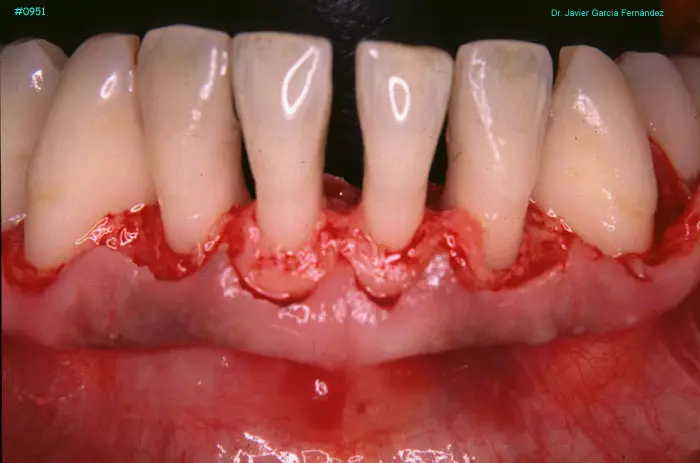

Atlas of Surgical Techniques in Periodontics. Chapter III. Atlas de Técnicas Quirúrgicas en Periodoncia